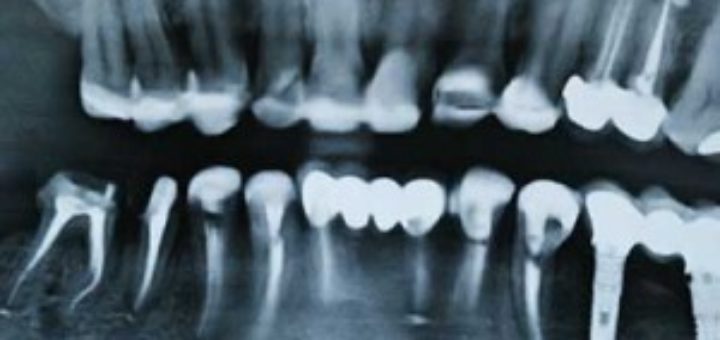

Cosmetic Dentistry Thailand Cost Dental tourism has grown tremendously in recent years, and one country that continues to attract global attention is Thailand. The rise in cosmetic dentistry Thailand cost benefits, advanced technologies, and...